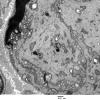

PERIPHERAL NEUROPATHY

0 PNS ARTIFACTS (5)